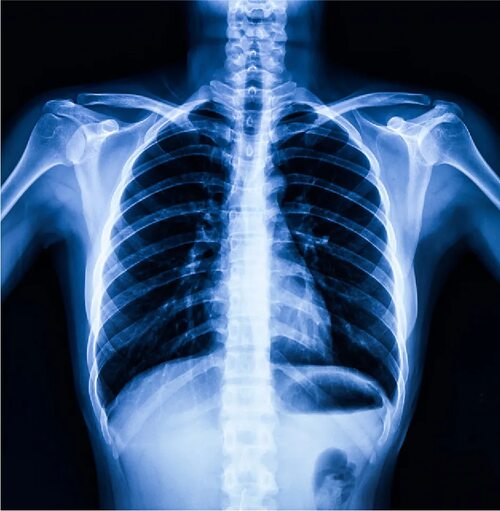

Легкие – это органы дыхания, расположенные в грудной клетке. Они играют важную роль в обеспечении организма кислородом и удалении углекислого газа. У каждого из нас есть два легкого, которые имеют сложную структуру.

Легкие состоят из миллионов маленьких воздушных пузырьков, называемых альвеолами, которые обеспечивают газообмен между воздухом и кровью. Каждое легкое окружено специальной оболочкой, называемой плеврой, которая помогает им двигаться свободно в грудной клетке. Кроме того, легкие имеют ветвящуюся систему бронхов, которые транспортируют воздух от гортани до альвеолов.

На фотографиях легких в грудной клетке можно увидеть их комплексную структуру, включая альвеолы, капилляры, бронхи и плевру. Изучение этих фото поможет вам лучше понять, как работают легкие и как они осуществляют газообмен.